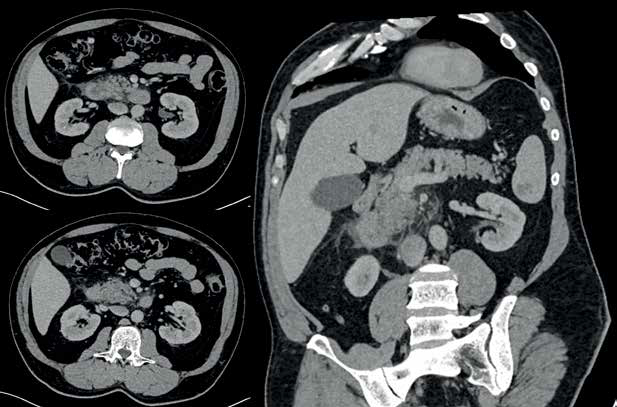

Figura 1 Tomografía axial computada de abdomen con contraste IV en donde se observa aumento del tamaño de la cabeza y el proceso uncinado del páncreas con estriación de la grasa y líquido peripancreático, con realce homogéneo.